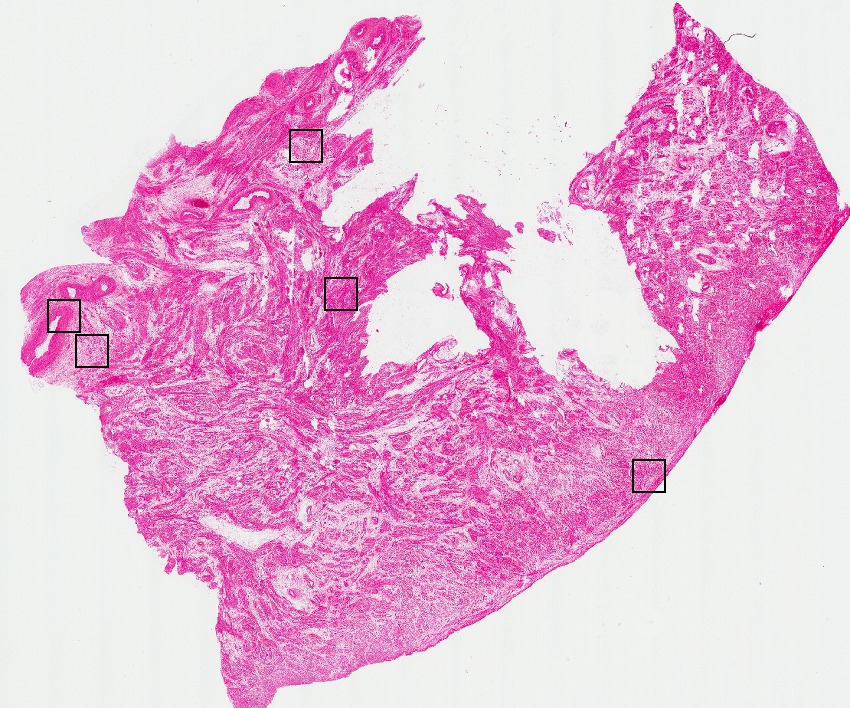

Smooth muscle cells:

85

Other cell types:

15